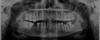

tapochka Опубликовано 17 февраля, 2013 Поделиться Опубликовано 17 февраля, 2013 (изменено) Здравствуйте уважаемые врачи!Какие возможны варианты лечения и протезирования? Что лучше сделать, пытаться восстановить или импланты? Изменено 17 февраля, 2013 пользователем tapochka Ссылка на комментарий

Bier Опубликовано 19 февраля, 2013 Поделиться Опубликовано 19 февраля, 2013 Еще верхний 6й справа - либо внедрять, либо подпиливать надо, нижний 7й слева - разрушение под десну - удалять и имплантат. Ссылка на комментарий

tapochka Опубликовано 27 февраля, 2013 Автор Поделиться Опубликовано 27 февраля, 2013 + консультация ортодонта была бы не лишней..появилось пару вопросов, помогите пожалуйста разобраться:правая сторона,там где вы писали про имплант, почему именно имплант? мостовидный протез не получится там сделать?наклоненная семерка - ее надо ставить ровно? или надо спилить и под коронку?левая сторона: реально ли на такие разрешенные зубы делать коронки? вроде бы врач взялся, но у меня сомнения. плюс ко всему 6-ка сильно разрушена и в процессе пломбировки каналов врач обнаружил граденулему (сорри, если не правильно написала) в общем, воспаление было там сильное, и врач не закладывал никаких лекарств, а просто запломбировал каналы, и сказал, что вроде как пройдет это воспаление..но болит уже неделю, пью антибиотики. это нормально, что так долго болит? и правильно ли сделал врач, что запломбировал воспаленный канал?заранее спасибо, я уже не знаю что и думать/к кому бежать, все говорят разные мнения.. Ссылка на комментарий